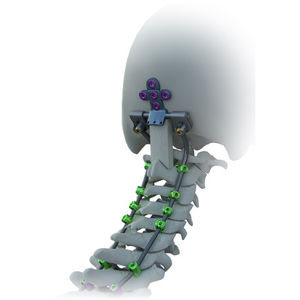

... Inestabilidad occipital y atlantoaxial, estenosis cervical, fracturas cervicales, luxaciones, tumores vertebrales, infecciones, lesiones de la unión cervicotorácica y otras afecciones que requieran cirugía combinada anterior y posterior. Características: Existe ...

... Proporciona inmovilización y estabilización de segmentos vertebrales como complemento de la fusión Facilita la fijación de tornillos en anatomías difíciles Tiene una estructura de perfil bajo Amplia gama de opciones de implantes Dispone de instrumentos ...

... Inestabilidades occipito-cervicales y de la columna cervical superior: - Artritis reumatoide - Anomalías congénitas - Afecciones postraumáticas - Tumores - Infecciones Inestabilidades de la columna cervical inferior y torácica superior: - ...

... fijación posterior y posterior con tornillos y la versatilidad de conexión con el sistema de fijación pedicular Vertice. Sistema compuesto por: – Barra occipitocervical de 3 y 4 agujeros; – Tornillo ...

... posterior de ATEC del Sistema de Fijación Solanas y el Sistema de Fijación Occipital Avalon proporciona una solución para abordar los retos de las cirugías occipito-cervico-torácicas posteriores (OCT). Características ...

... PLACAS DE VARILLA PARA ARTRODESIS OCCIPITO-CERVICAL El sistema J.O.C. permite realizar una artrodesis occipito-cervical posterior. - ABORDAJE POSTERIOR - FIJACIÓN CERVICAL - TITANIO Ti 6-AL4-V Indicaciones ...